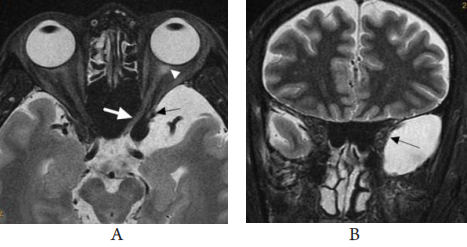

图7 轴位(A)和冠状位(B)头颅MRI图像

Figure 7 Axial(A)and coronal(B)cranial MRI images

(A)左侧颞极蛛网膜囊肿压迫眶外壁(黑箭头),左侧蝶窦气化良好,视神经管穿过蝶窦腔(白箭),球后部视神经 T2WI呈稍高信号(白箭头)。(B) 左侧颞极蛛网膜囊肿压迫眶外壁(黑箭头)。

(A)An arachnoid cyst in the left temporal pole is causing compression of the lateral orbital wall(black arrow). The left sphenoid sinus is well aerated, and the optic nerve canal passes through the sphenoid sinus cavity(white arrow). There is a slightly high signal intensity in the posterior part of the optic nerve on T2-weighted imaging(white arrowhead). (B) An arachnoid cyst in the left temporal pole is causing compression of the lateral orbital wall (black arrow).